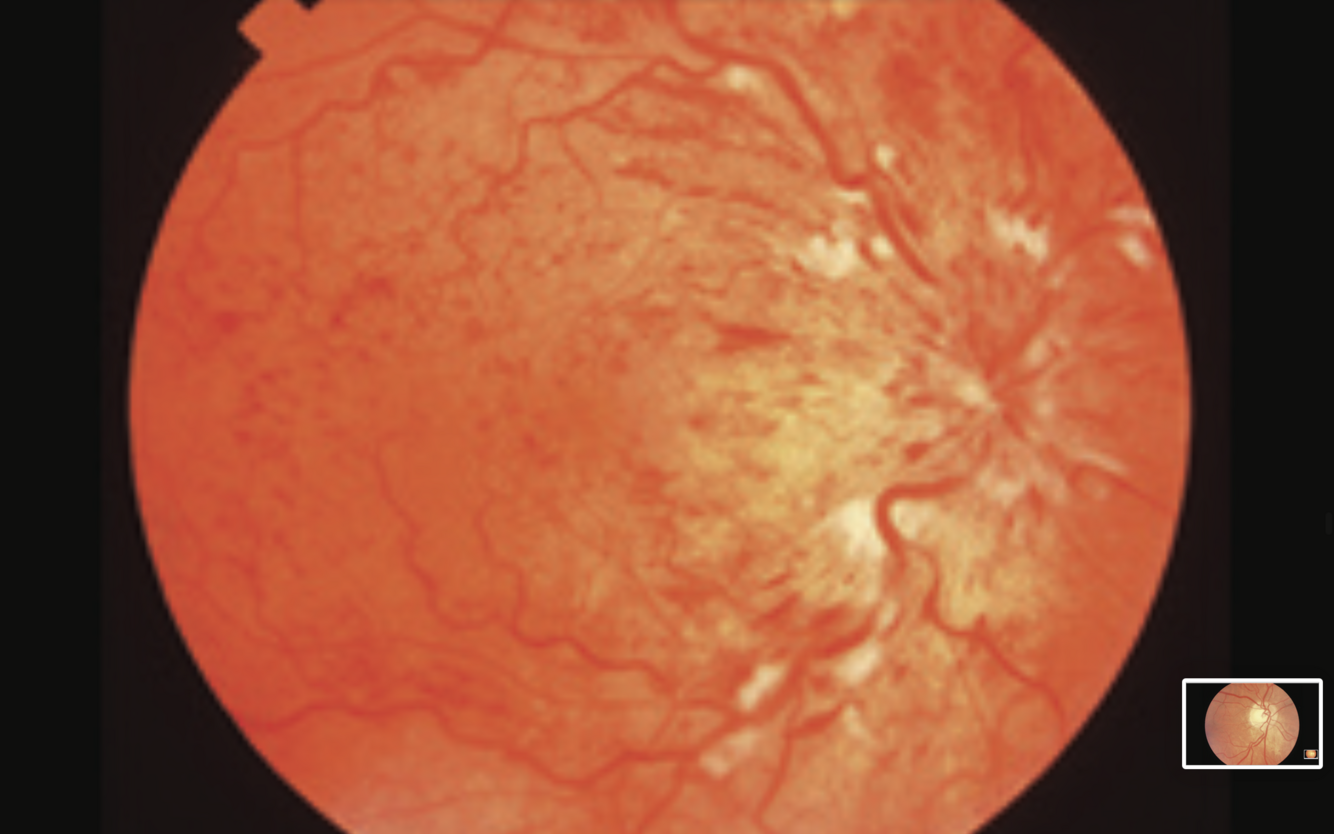

Pre-proliferative Diabetic Retinopathy

-cotton wool spots

- dot and blot haemorrhages